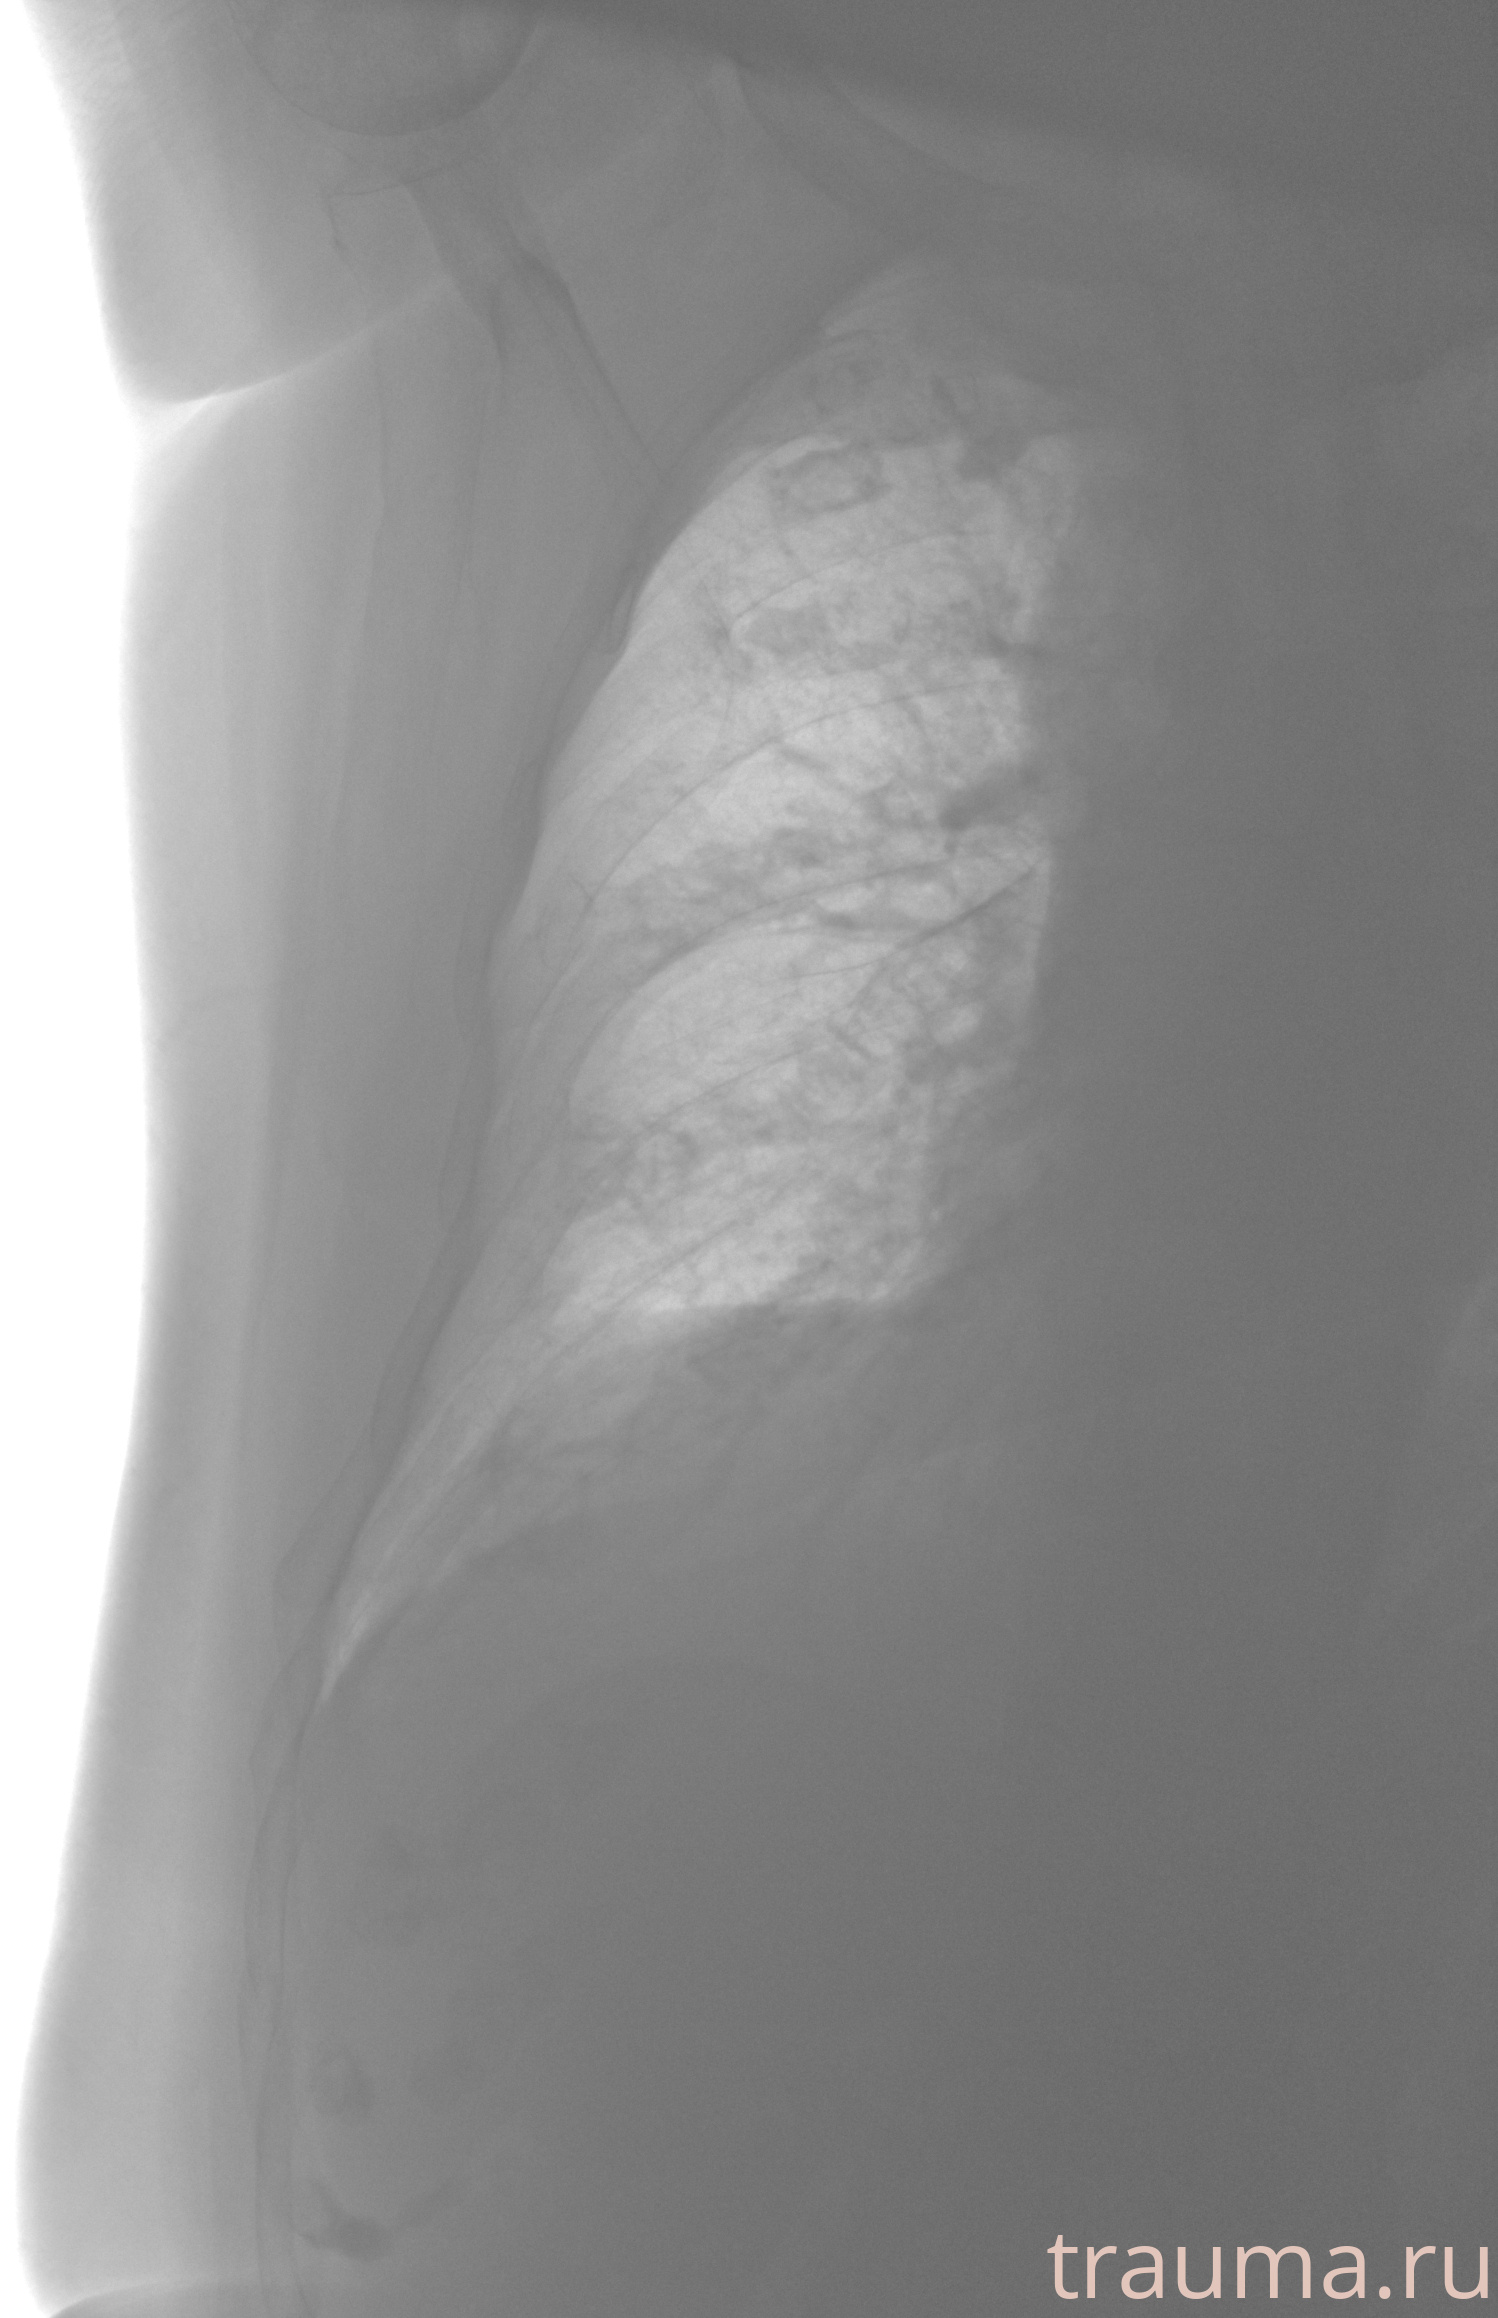

Рентген на дому: по вашему адресу приезжает врач-рентгенолог, травматолог-ортопед с мобильным рентгеновским аппаратом, проводит диагностику травмы или заболевания, делает необходимые рентгенограммы, дает рекомендации по дальнейшему лечению. Получить качественные снимки в домашних условиях возможно благодаря уникальной методике, разработанной МосРентген Центром для института  Склифосовского

при переломе шейки бедра и пневмонии от компании МосРентген Центр - партнера Института имени Склифосовского